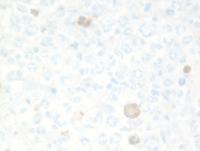

Low and High power of histology of GZL

Sections from the right axillary lymph node demonstrate effacement of the lymph node architecture by a diffuse lymphohistiocytic infiltrate with patchy areas of necrosis and multiple vaguely perivascular clusters and singly scattered large Hodgkin-like cells with wreath-like nuclei somewhat reminiscent of lymphomatoid granulomatosis, grade 3.

The histologic features are intermediate between cHL, LyG grade 3 and T/HRLBCL without any areas displaying sheets of large centroblastic or immunoblastic cells.

GZL-Low-power

GZL-High-power